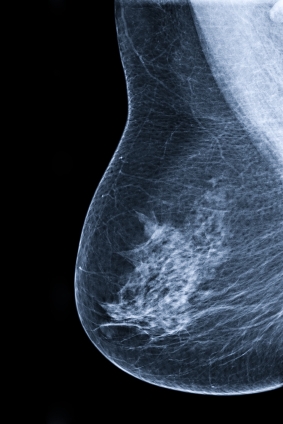

ДИАГНОСТИКА

Для постановки диагноза врач изучает анамнез болезни, жалобы больной, клиническую картину заболевания, проводит физикальный осмотр, лабораторные и инструментальные исследования: маммографию, узи молочной железы, пункционную биопсию опухоли, для исключения метастазов в другие органы - радиоизотопное исследование костей (сцинтиграфию), УЗИ органов брюшной полости, рентгенографию грудной клетки, клинический и биохимический анализы крови и др.